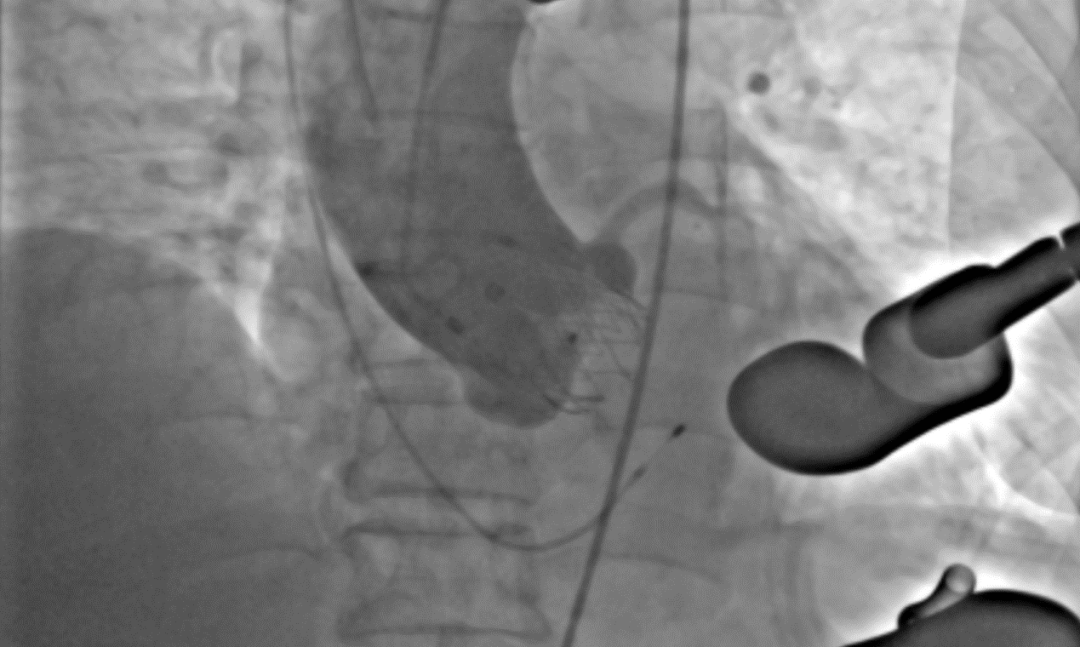

术后DSA影像图